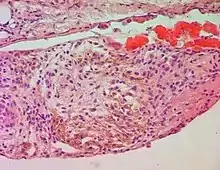

Siderophages (brown spots) in an endometriotic focus.